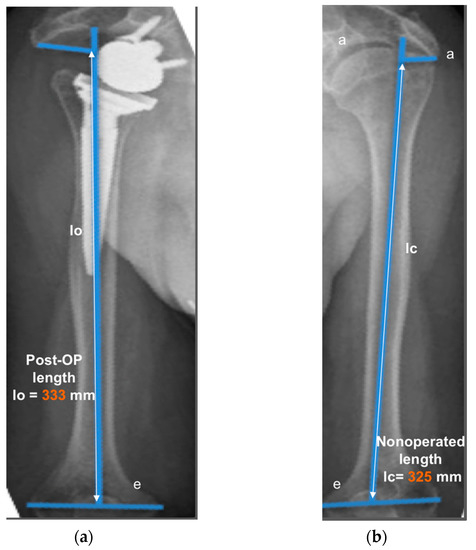

2.3. Radiographic Evaluation

- Lädermann, A.; Williams, M.D.; Melis, B.; Hoffmeyer, P.; Walch, G. Objective evaluation of lengthening in reverse shoulder arthroplasty. J. Shoulder Elbow Surg. 2009, 18, 588–595. [Google Scholar] [CrossRef]